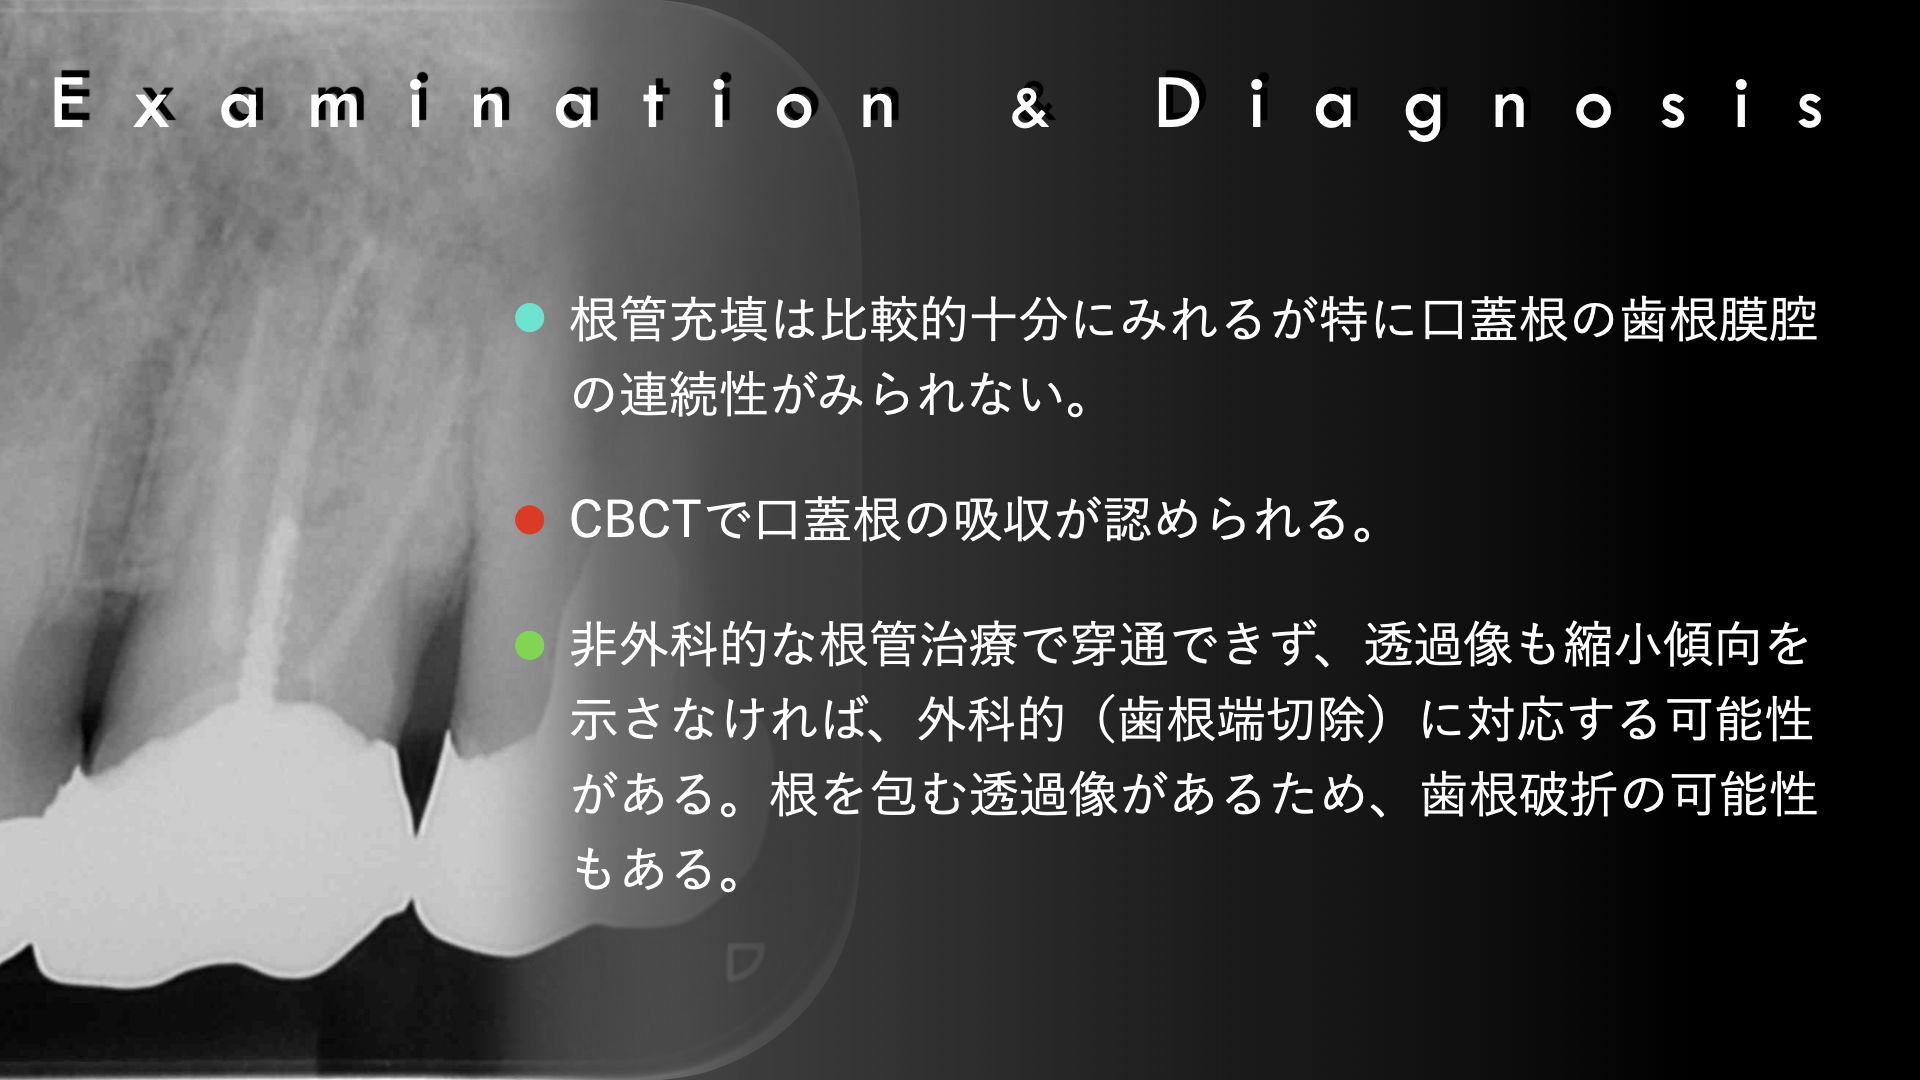

右の画像のCT上で根尖部にかなり大きな透過像があります。

根管治療はマイクロスコープを使用し、根管内は綺麗になった。と判断したので2回でMTAセメントにより根管充填をおこないました。

噛み合わせの反対側(下顎)はインプラント治療をおこなっており、経過をみていましたが全く変化がありませんでした。

患者さんの都合もあり1年後に歯根端切除(外科的歯内療法)をおこなうことになりました。

教科書によると、この部位は適応症でなく、一般的には意図的再植の適応症にはなりますが、このような歯根が離開している歯を一度抜歯するのは破折のリスクがあります。

適応症ではないのは大口蓋動脈の存在です。

論文より今回のケースは安全であると判断し、歯根端切除で対応しました。

術後、歯根は骨に囲まれるように治癒にしました。

このように非外科的な治療のみでは治癒に導けない場合は、外科的歯内療法で保存できる可能性があります。